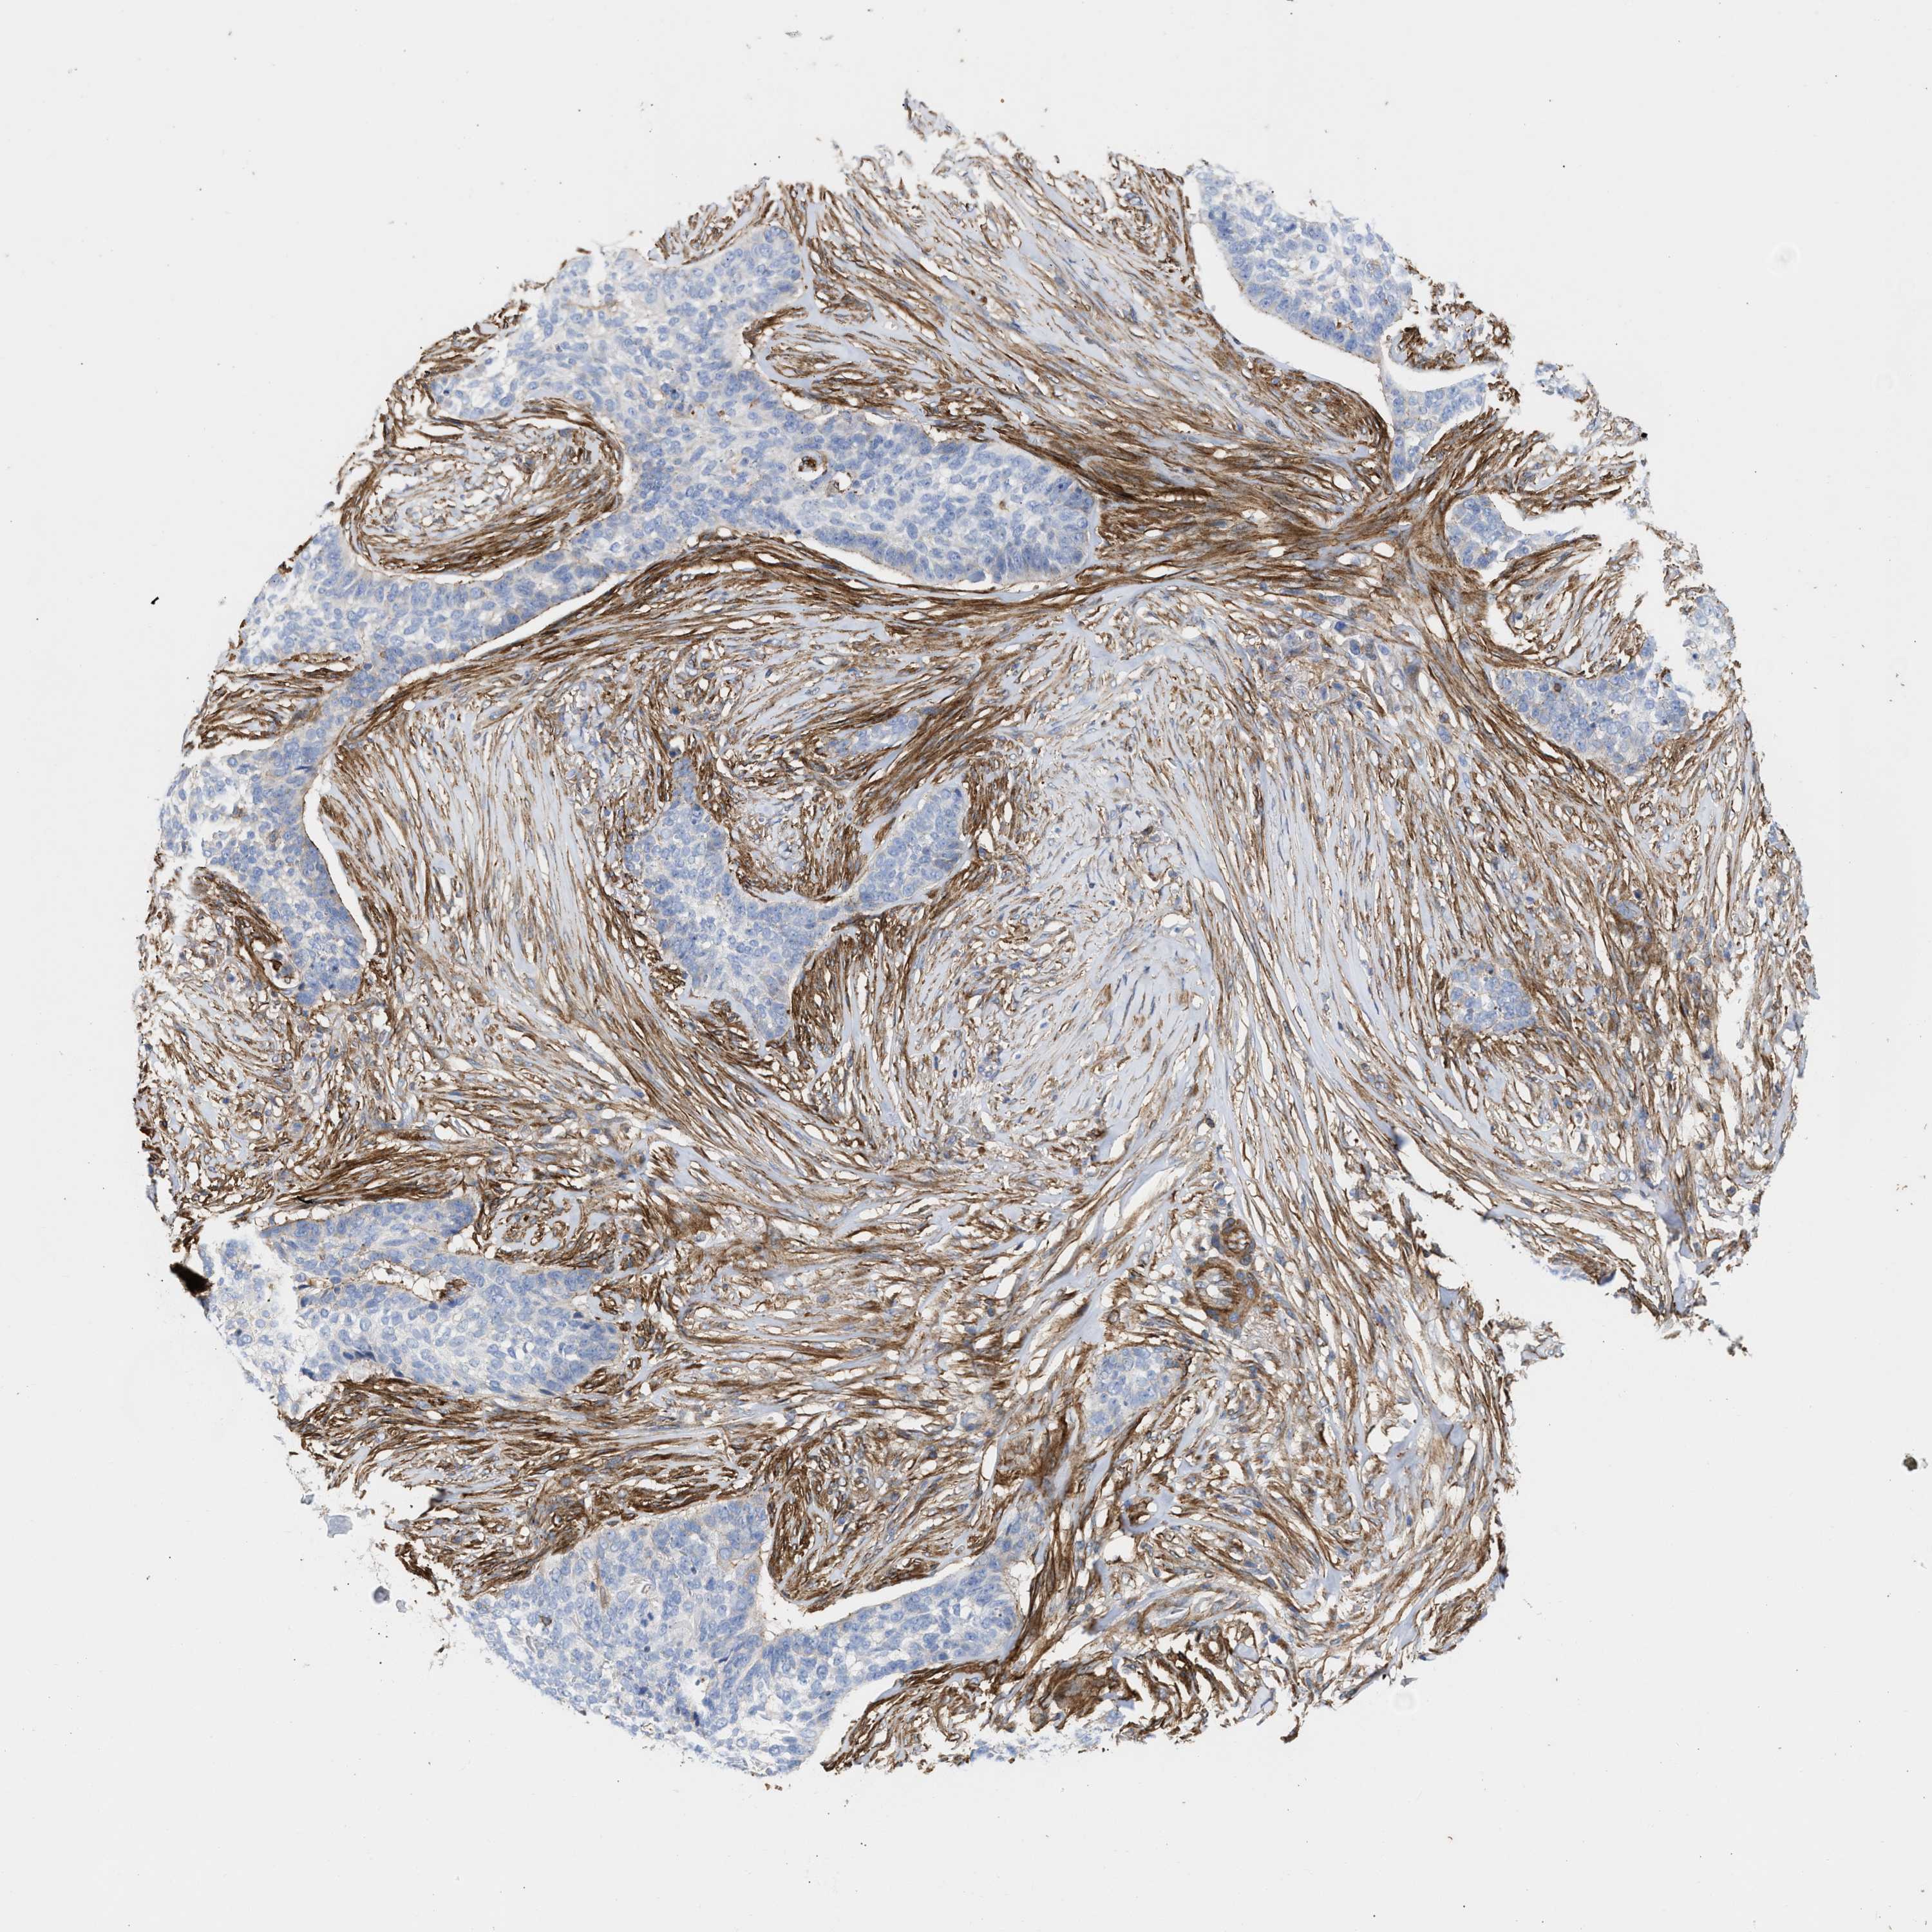

SKIN CANCER - Protein expressioni

A mouse-over function shows sample information and annotation data. Click on an image to view it in a full screen mode. Samples can be filtered based on level of antibody staining by selecting one or several of the following categories: high, medium, low and not detected. The assay and annotation is described here.

Antibody stainingi

Antibody staining in the annotated cell types in the current human tissue is reported as not detected, low, medium, or high, based on conventional immunohistochemistry profiling in selected tissues. This score is based on the combination of the staining intensity and fraction of stained cells.

Each image is clickable and will lead to virtual microscopy that enables deeper exploration of all samples and also displays staining intensity scores, fraction scores and subcellular localization as well as patient and tissue information for each sample.

Antibody HPA021823

Antibody HPA064677

Basal cell carcinoma

Squamous cell carcinoma, NOS

Squamous cell carcinoma, metastatic, NOS

BCC, high aggressive